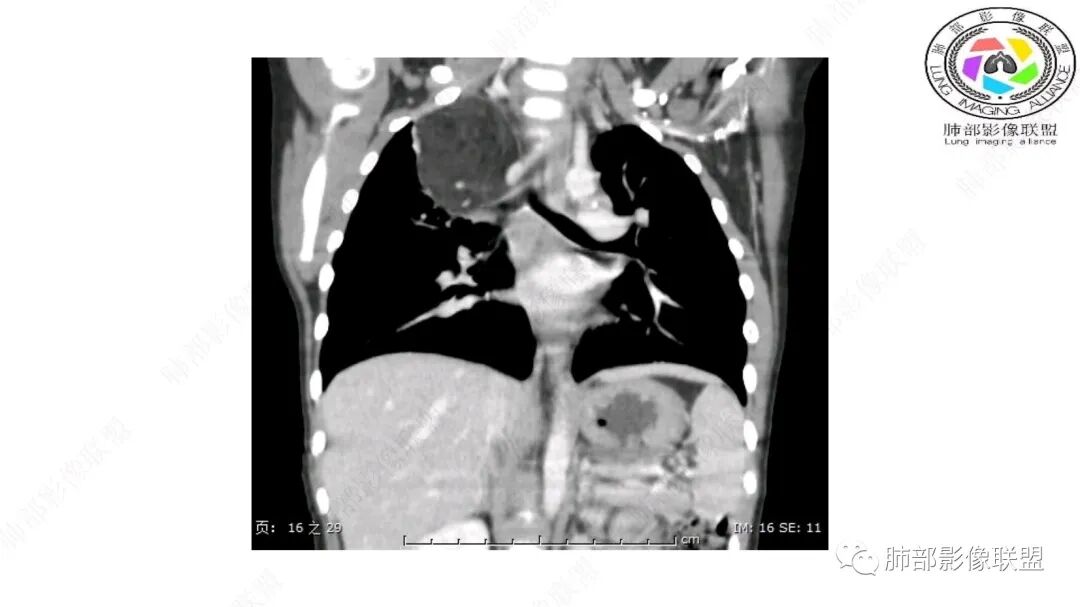

右上纵隔混杂密度肿块,边缘光整,与纵隔分界清,其内多发脂肪密度,增强无明显强化,其内血管穿行,考虑纵隔脂肪母细胞瘤,鉴别畸胎瘤,脂肪肉瘤。

三岁小儿,右侧纵隔巨大脂肪密度肿块,肺动脉穿行其中,密度欠均匀,未见明确实性成分,纵隔脂肪母细胞瘤,冬眠瘤鉴别纵隔脂肪增多症(多弥漫对称)。

患儿3岁 咳嗽检查发现纵隔占位。右肺上叶受压表现,占位以脂肪组织密度为主,似见分隔,首先考虑为脂肪母细胞瘤,鉴别脂肪瘤,畸胎瘤。

病灶属于交界区,主体位于肺内,占位效应明显,前方突入胸壁,胸腺受压变形,胸膜显示欠清楚;病灶包绕上叶肺动脉;似乎有体动脉供血。符合肺内的点:包绕上叶肺动脉分支;符合纵隔的点:前方似乎突入胸壁,与胸腺关系比较密切,但是与上腔静脉的关系提示病灶不支持纵隔来源,前纵隔的常规会将上腔静脉受压后移、外移,这是不符合的。

1.右上肺-纵隔交界区巨块影,主体位于右肺一侧,紧贴胸腺、头臂干、右锁骨下动脉、上腔静脉、奇静脉等,不能分离,但病灶整体边界清楚。注意上述相邻腔静脉等结构未见受压变形,纵隔亦未见明显向左推移,至少提示两点:

2.肺动脉穿行也许是肺内来源最重要支持点!

脂肪母细胞瘤由成熟程度不同的脂肪组织、纤维间隔、黏液基质、小血管丛等间质成分组成,以脂肪组织与黏液样基质为主,其影像学表现取决于上述组织成分。典型的CT和MRI表现为:前后纵隔均可发生,常见于前纵隔;肿块大小不一,直径多在3cm~7cm,密度均匀,CT值呈水样或脂肪密度,脂肪组织密度或信号为主的肿块,其内密度或信号不均匀,可见粗细不一的分隔影,且有结节、片状影,后者可呈轻中度强化;结节状肿瘤包膜完整;弥漫性者包膜不明显,常呈浸润性生长;周围结构为受压和推移改变,可有少量胸腔积液,淋巴结无增大。